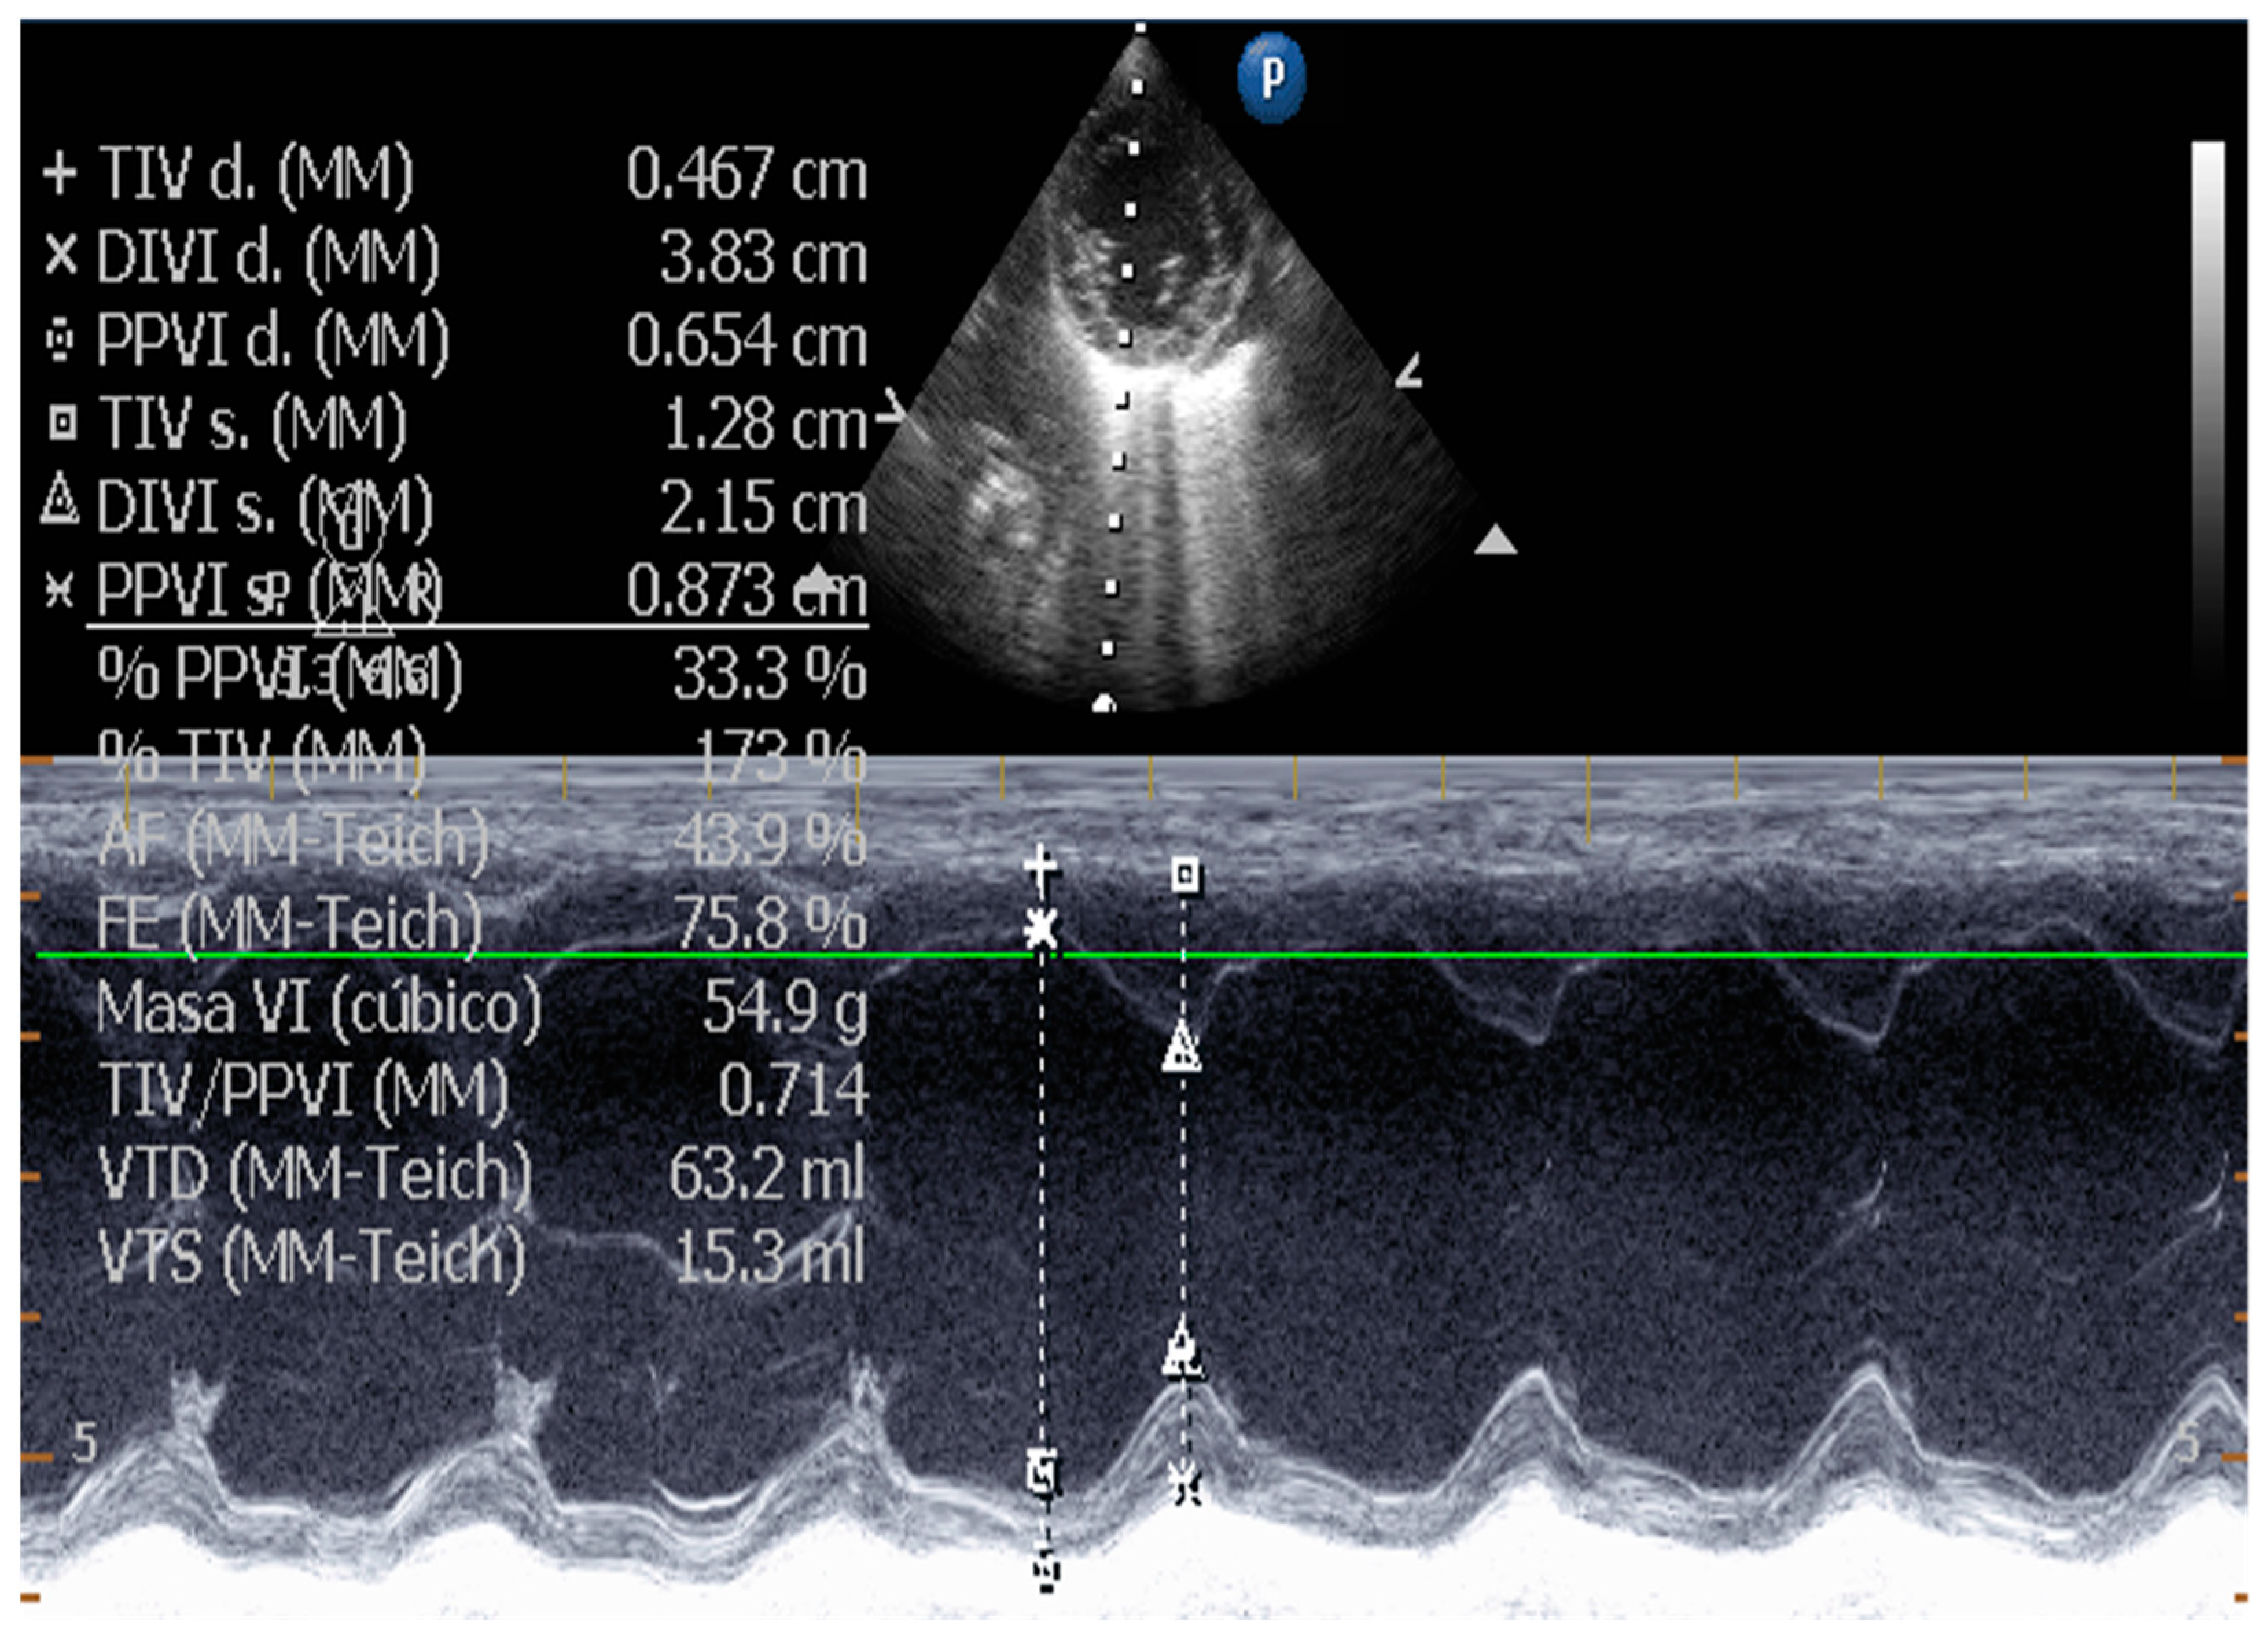

5.1. Echocardiographic Measurements on DCM

5.1.1. Measurement of Left Ventricular Volume by Simpson’s Method of Disks and Left Ventricular M-Mode

- Bonagura, J.D.; Visser, L.C. Echocardiographic assessment of dilated cardiomyopathy in dogs. J. Vet. Cardiol. 2022, 40, 15–50. [Google Scholar] [CrossRef] [PubMed]

- Esser, L.C.; Borkovec, M.; Bauer, A.; Häggström, J.; Wess, G. Left ventricular M-mode prediction intervals in 7651 dogs: Population-wide and selected breed -specific values. J. Vet. Intern. Med. 2020, 34, 2242–2252. [Google Scholar] [CrossRef]

| Measurement of Left Ventricular Volume | M-mode echocardiography is widely used in canine cardiology, but its utility is debated. American Society of Echocardiography recommends against using linear measurements in the human patient. SMOD is recommended [100,102,103]. |